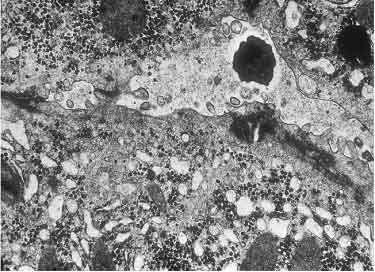

Histologisch bietet die Schwangerschaftsleber

ein normales Bild. Elektronenoptisch finden sich

jedoch bei ca. drei Vierteln der Schwangeren im letzten Trimenon

mitochondriale Veränderungen in Form von Vergrößerungen,

Verformungen und kristallinen Einschlüssen. Es dürfte

sich um adaptive Veränderungen handeln, wahrscheinlich bedingt

durch die erhöhten Steroidhormonspiegel, denen kein Krankheitswert

zukommt und die sich nach der Geburt vollständig zurückbilden

(Abb. 1.1) (69, 70, 74). Eine besondere Ausprägung

erfahren diese strukturellen Alterationen der Mitochondrien im Rahmen

der intrahepatischen Schwangerschaftscholestase (s. Kap. 1.3.1.),

möglicherweise sind sie auch pathogenetisch bedeutsam bei der

akuten Schwangerschaftsfettleber (s. Kap. 1.3.3).

Abb. 1.1 Ausschnitt einer Leberparenchymzelle

bei ungestörter Schwangerschaft 8. Monat. Neben wenigen, normal

strukturierten Mitochondrien finden sich zahlreiche vergrößerte

Mitochondrien mit kristallinen Innenstrukturen und dichtem Cristae-Besatz.

Bis auf eine geringe Vakuolisierung des endoplasmatischen Retikulums

sind die übrigen Zellorganellen normal. Vergr. 13800fach.